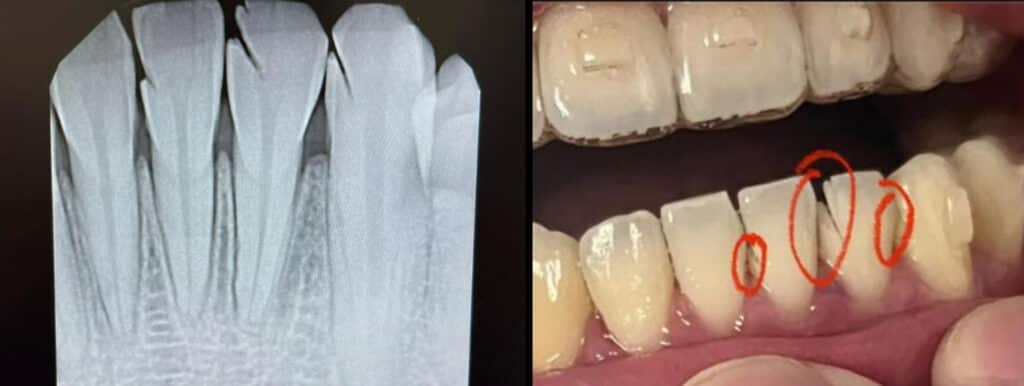

Discs provide a quicker alternative to achieving space, but if not handled properly, can cause trauma to the teeth, tongue, lips, or cheeks (Figure 1). In addition, because the discs are usually not flexible, the contact achieved may be flat, not the desired “smaller version of the tooth,” advocated by Sheridan.

Burs offer another quick alternative to gaining space, but the typical design falls short of achieving accurate enamel reduction and an ideal contact. The typical bur used for IPR is flame-shaped (Figure 2). If it is simply swiped through the contact, it can create an anatomical problem where the incisal portion of the contact is too wide (Figure 3). In addition, bur manufacturers don’t commonly label their products with the exact diameter of the bur at each section, meaning that the tip has a smaller diameter than the base, and the practitioner typically does not know those dimensions. If aligner prescriptions call for 0.2, 0.3, 0.4, or 0.5 mm of space between the contacts, typical burs used for IPR cannot easily create those specific amounts without constantly measuring the sites.